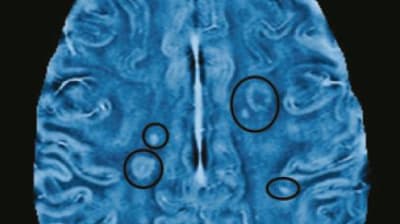

Treating Brain Clots Robotically